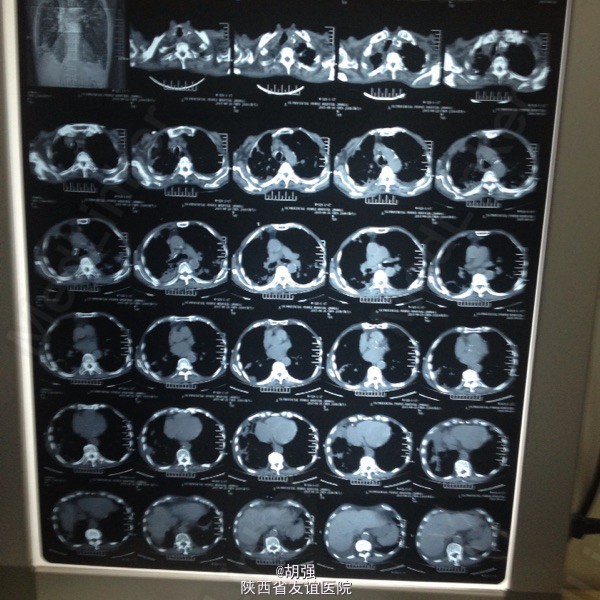

老年男性患者七十六岁。 主诉:反复咳嗽、咳痰10年,加重2月。 现病史:患者10年前受凉后出现咳嗽、咳痰,于当地医院给抗感染治疗后症状消失。此后每遇劳累或者季节交替时,反复出现咳嗽、咳痰、胸闷、气短,且逐年加重,多次住院,行胸部CT、肺功能、血气分析等相关检查,诊断为:慢性阻塞性肺疾病急性加重期,给于抗感染、平喘治疗后均能缓解(具体用药及剂量不详)。2月前受凉后,咳嗽、咳痰、气短症状加重,咳大量白色黏痰,于外院抗感染对症治疗效果不佳,遂来我院。 既往有甲状腺功能亢进病史8年,继发心房纤颤,行I131治疗;有腔隙性脑梗死病史5年。

查体:口唇略紫绀,口腔黏膜无充血、糜烂、溃疡;颈静脉怒张,桶状胸,两侧呼吸动度及语颤减弱,叩诊呈过清音,两肺呼吸音粗糙,可闻及哮鸣音及湿性啰音。心率110次/分,律不齐,心音强弱不等,各瓣膜听诊区未闻及病理性杂音。腹平软,无压痛,肝脾肋下未及,双下肢水肿。 血常规: 白细胞14.01XE9/L、中性细胞比率91%、血红蛋白170g/L、血小板370X10E9/L。

慢性阻塞性肺疾病急性加重期,肺结核?肺真菌病?支气管扩张?慢性肺源性心脏病,心功能IV级,甲状腺功能亢进症,I131治疗后,心房纤颤,脑梗死。 外院给予特治星及氟康唑治疗效果不佳。入院后给予舒普深3.0静注2次/日联合莫西沙星片o.4口服1次/日,多索茶碱0.2十甲泼尼龙20mg2次/日,镁极化液250ml十异舒吉20mg静点,酚妥拉明10mg静点及强心、利尿治疗后好转。

复查血常规正常,血气分析提示:低氧血症,代射性碱中毒,电解质示:钾低。考虑:代谢性碱中毒由低钾所致。